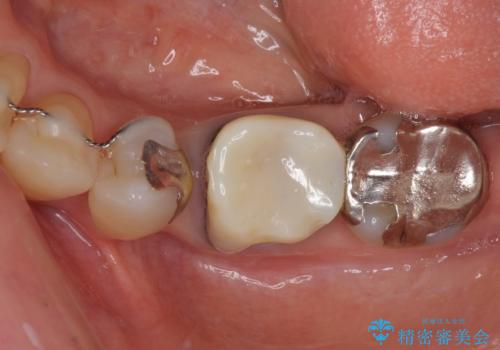

- 矯正治療を行った歯科医院で装着した前歯の仮歯が不快とのことで来院された患者様です。

仮歯自体はとても綺麗でしたが、2本の歯が欠損している部分に上唇小帯が入り込んでいたため、歯肉形成を行った上で仮歯を調整し、オールセラミックブリッジを装着することとしました。

他にも治療が必要な歯があったため、合わせてセラミッククラウンやセラミックインレーで治療することとしました。